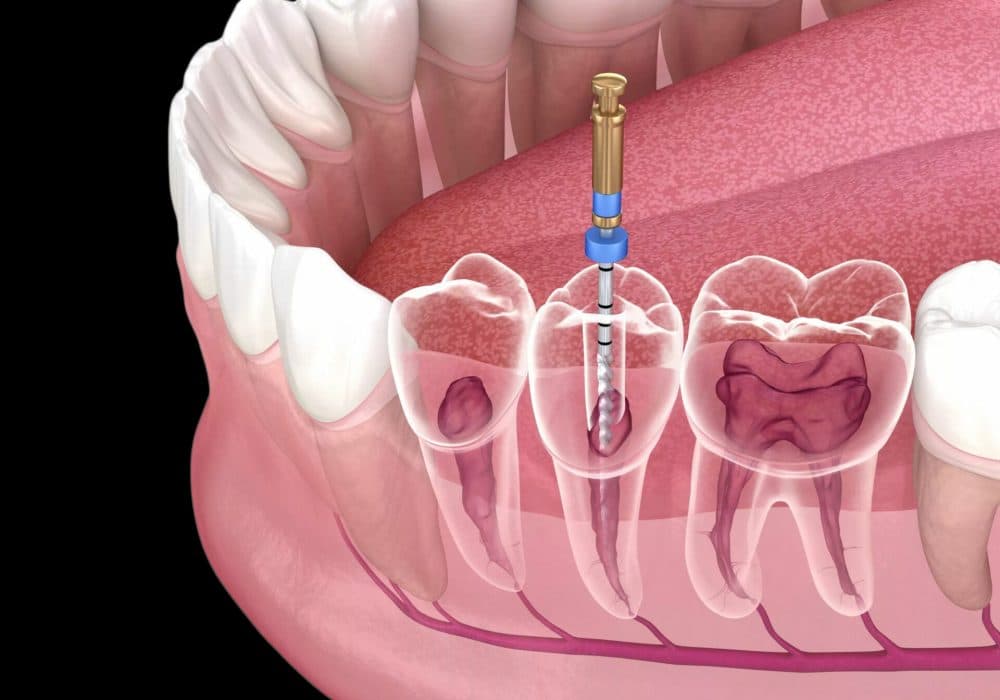

Root Canal Treatment

Save infected teeth with gentle, pain-free root canal procedures using modern techniques.

Learn More About Root Canal Treatment